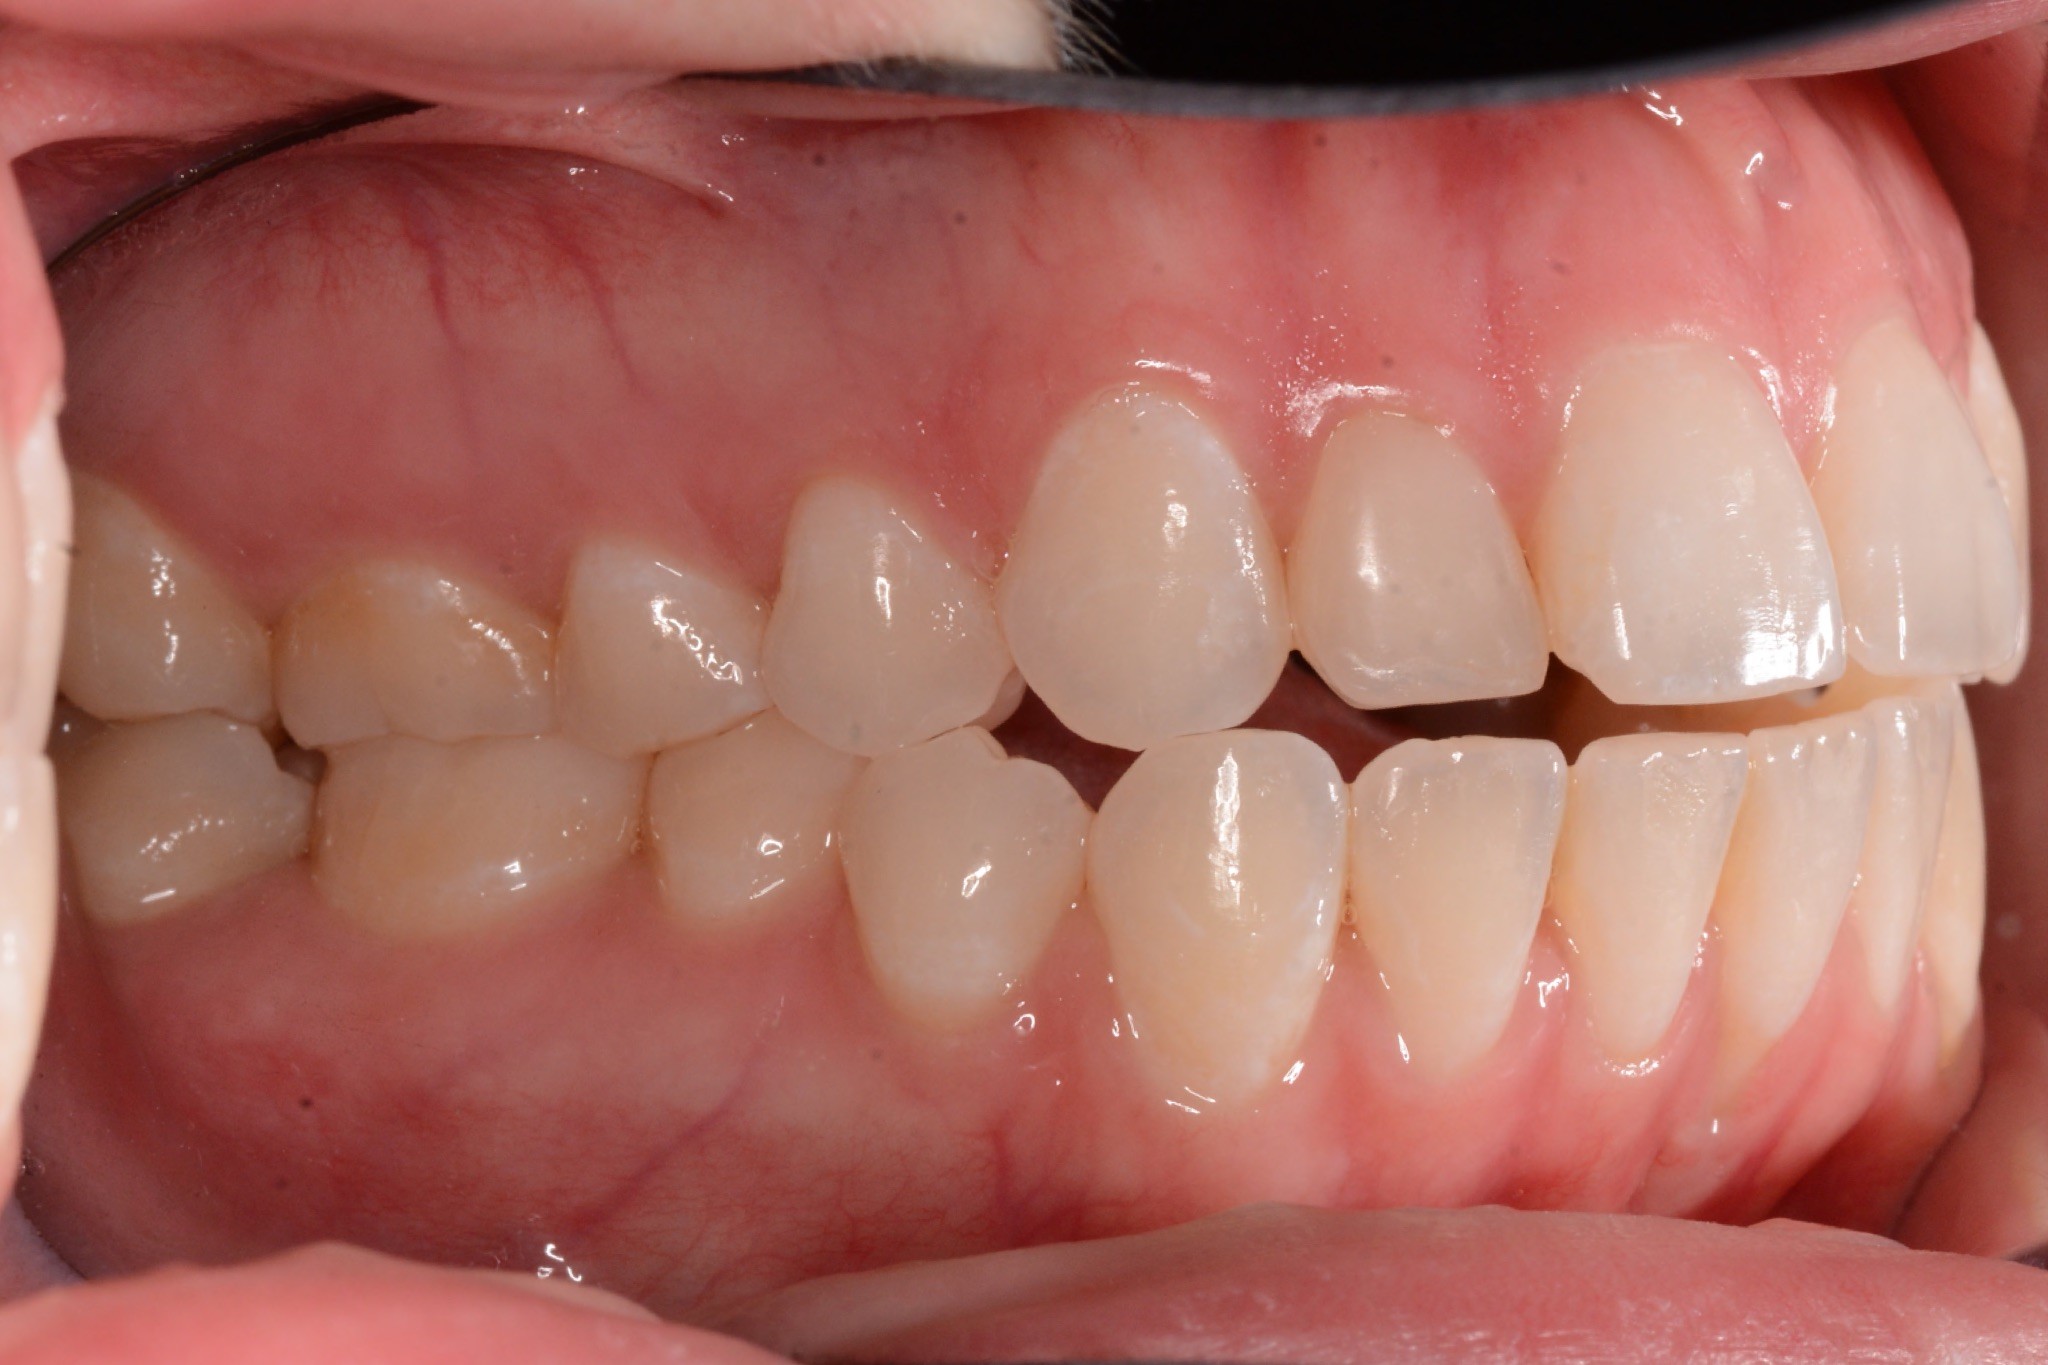

Final results

INTRAORAL